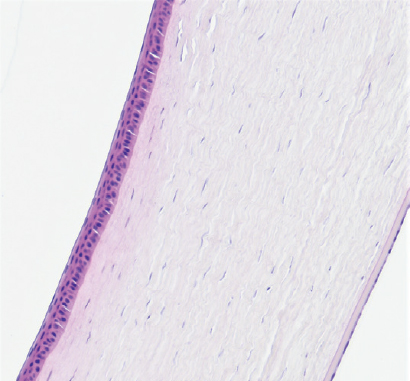

Кросслинкинг. На данном сроке эксперимента строма роговицы в месте воздействия уплотнена на 45 %. Эпителий на всём протяжении обычного строения. Десцеметова мембрана и энодотелий без изменений (рис. 7).

Рис. 7. Фрагмент роговицы после воздействия в подруппе 1а. Кросслинкинг. Окраска гематоксилином и эозином. Увеличение ×100

Fig. 7. Fragment of the cornea after exposure in subgroup 1a. Crosslinking. Stained with hematoxylin and eosin. Magnification ×100